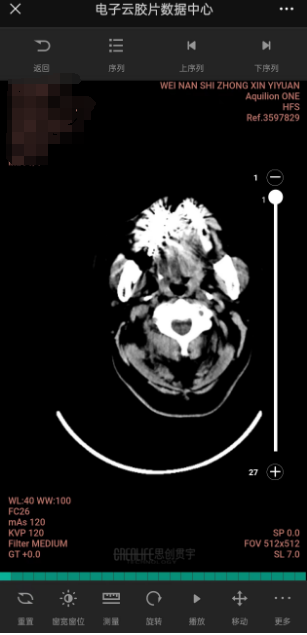

云胶片是互联网+医疗政策下的创新服务模式,是基于移动互联网、云计算、区块链和大数据技术的一种新型医学影像服务。简单来说,云胶片就是存储在云端的电子胶片,可实现胶片即存即取、即用即看、智能终端调阅等功能,达到无线连接患者、医生和医院的作用。支持CT、MR、DR、超声等全部检查影像和报告调阅。可在手机终端授权范围内不限次数查看、下载。

5、点击检查影像即可查看本次检查所有影像